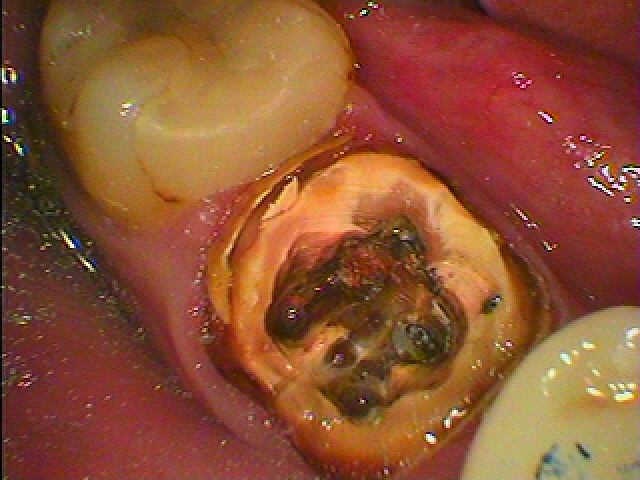

かぶせを外してオールセラミッククラウンへのやり変え|お知らせ |広島市安佐南区の歯科医院 かぶせを外してオールセラミッククラウンへのやり変え トップ お知らせ・ブログ お知らせ かぶせを外してオールセラミッククラウンへのやり変え かぶせを外してオールセラミッククラウンへのやり変え この被せを外していきます 境目が合わなくなっているのと根が化膿しています 被せを外していきました 中はドロドロとして悪くなっています 根幹治療から行い、しっかりと中をきれいにしていきます 中をきれいにし、薬を詰めていきます ファイバーコアにて築造を行っています セレックオールセラミックにて修復しています 綺麗に仕上がりました Web診療予約 初めての方へ 選ばれ続ける理由 院内設備について 歯が痛いしみる一般歯科 歯がぐらぐらする歯周病 健康な歯を保ちたい予防歯科 子供の虫歯予防をしたい小児歯科 銀歯をセラミックに審美歯科 白い歯を目指しませんか?ホワイトニング 矯正専門医がいるので安心矯正歯科 抜けた歯を補いたいインプラント・入れ歯 医院案内 スタッフ紹介 メリィハウス歯科クリニックオフィシャルホームページ ラベンダー歯科クリニックオフィシャルホームページ お知らせ・ブログ ホーム 診療科目 一般歯科 歯周病治療 予防治療 小児歯科 審美治療 ホワイトニング 矯正歯科 入れ歯・インプラント マウスピース矯正 初めての方へ 院長・スタッフ 設備紹介 医院案内・アクセス メニューを閉じる